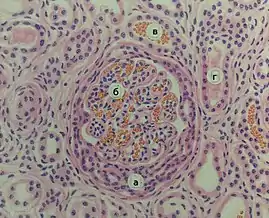

![]() Мікрофотографія біоптату нирки хворого з гострим прогресивним гломерулонефритом. Фарбування гематоксиліном-еозином. Мікрофотографія біоптату нирки хворого з гострим прогресивним гломерулонефритом. Фарбування гематоксиліном-еозином. | |

При гострому гломерулонефриті нирки збільшені, бліді, кіркова речовина на поверхні з дрібними червоними вкрапленнями. Гістологічно в більшості випадків проявляється імунокомплексний інтракапілярний проліферативний гломерулонефрит, який у своєму розвитку проходить екссудативну, екссудативно-проліферативну та проліферативну фази. Рідко зустрічаються екстракапілярна геморагічна та некротична форми[18].

При підгострому гломерулонефриті зі швидким прогресуванням і летальним результатом протягом тижнів чи місяців (злоякісний гломерулонефрит) нирки є великими, жовто-сірими з множинними дрібними геморагіями. Мікроскопічна картина є характерною: екстракапілярний продуктивний гломерулонефрит, або гломерулонефрит із півмісяцями, розвиток якого є пов'язаним із впливом імунних комплексів та антитіл[19].